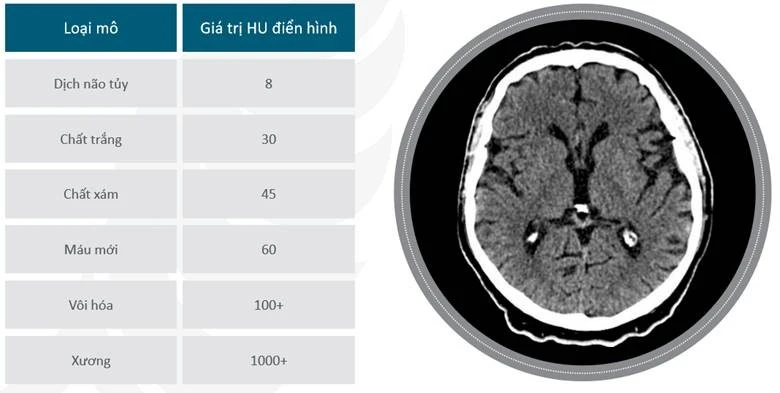

Nước cất được xác định tùy ý bằng 0 HU và không khí là -1000 HU. Giới hạn trên có thể lên tới 1000 đối với xương, 2000 đối với xương đặc như ốc tai và hơn 3000 đối với kim loại như thép hoặc bạc.

Từ đó ta chia thành thang điểm HU hiển thị dưới dạng tông màu xám. Mô dày đặc hơn, với sự hấp thụ chùm tia X lớn hơn, có giá trị dương và xuất hiện sáng; mô ít đặc hơn, ít hấp thụ chùm tia X hơn, có giá trị âm và xuất hiện tối.

Một số ví dụ về HU

Chúng ta đều biết: Chỉ số HU (Hounsfield unit) là chỉ số đo lường chất lượng xương trong chụp CBCT. Nhìn vào con số HU, nhà lâm sàng có thể đánh giá được chất lượng D1, D2, D3, D4 hay các mô giải phẫu xung quanh vị trí Implant, mức độ tích hợp quanh Implant.

– Không khí: HU = -1000

– Mô mỡ: HU = -120

– Cancellous Bone: HU = 400

– Cortical Bone: HU = 500~1900

– Mô mềm: HU = +100 to +300